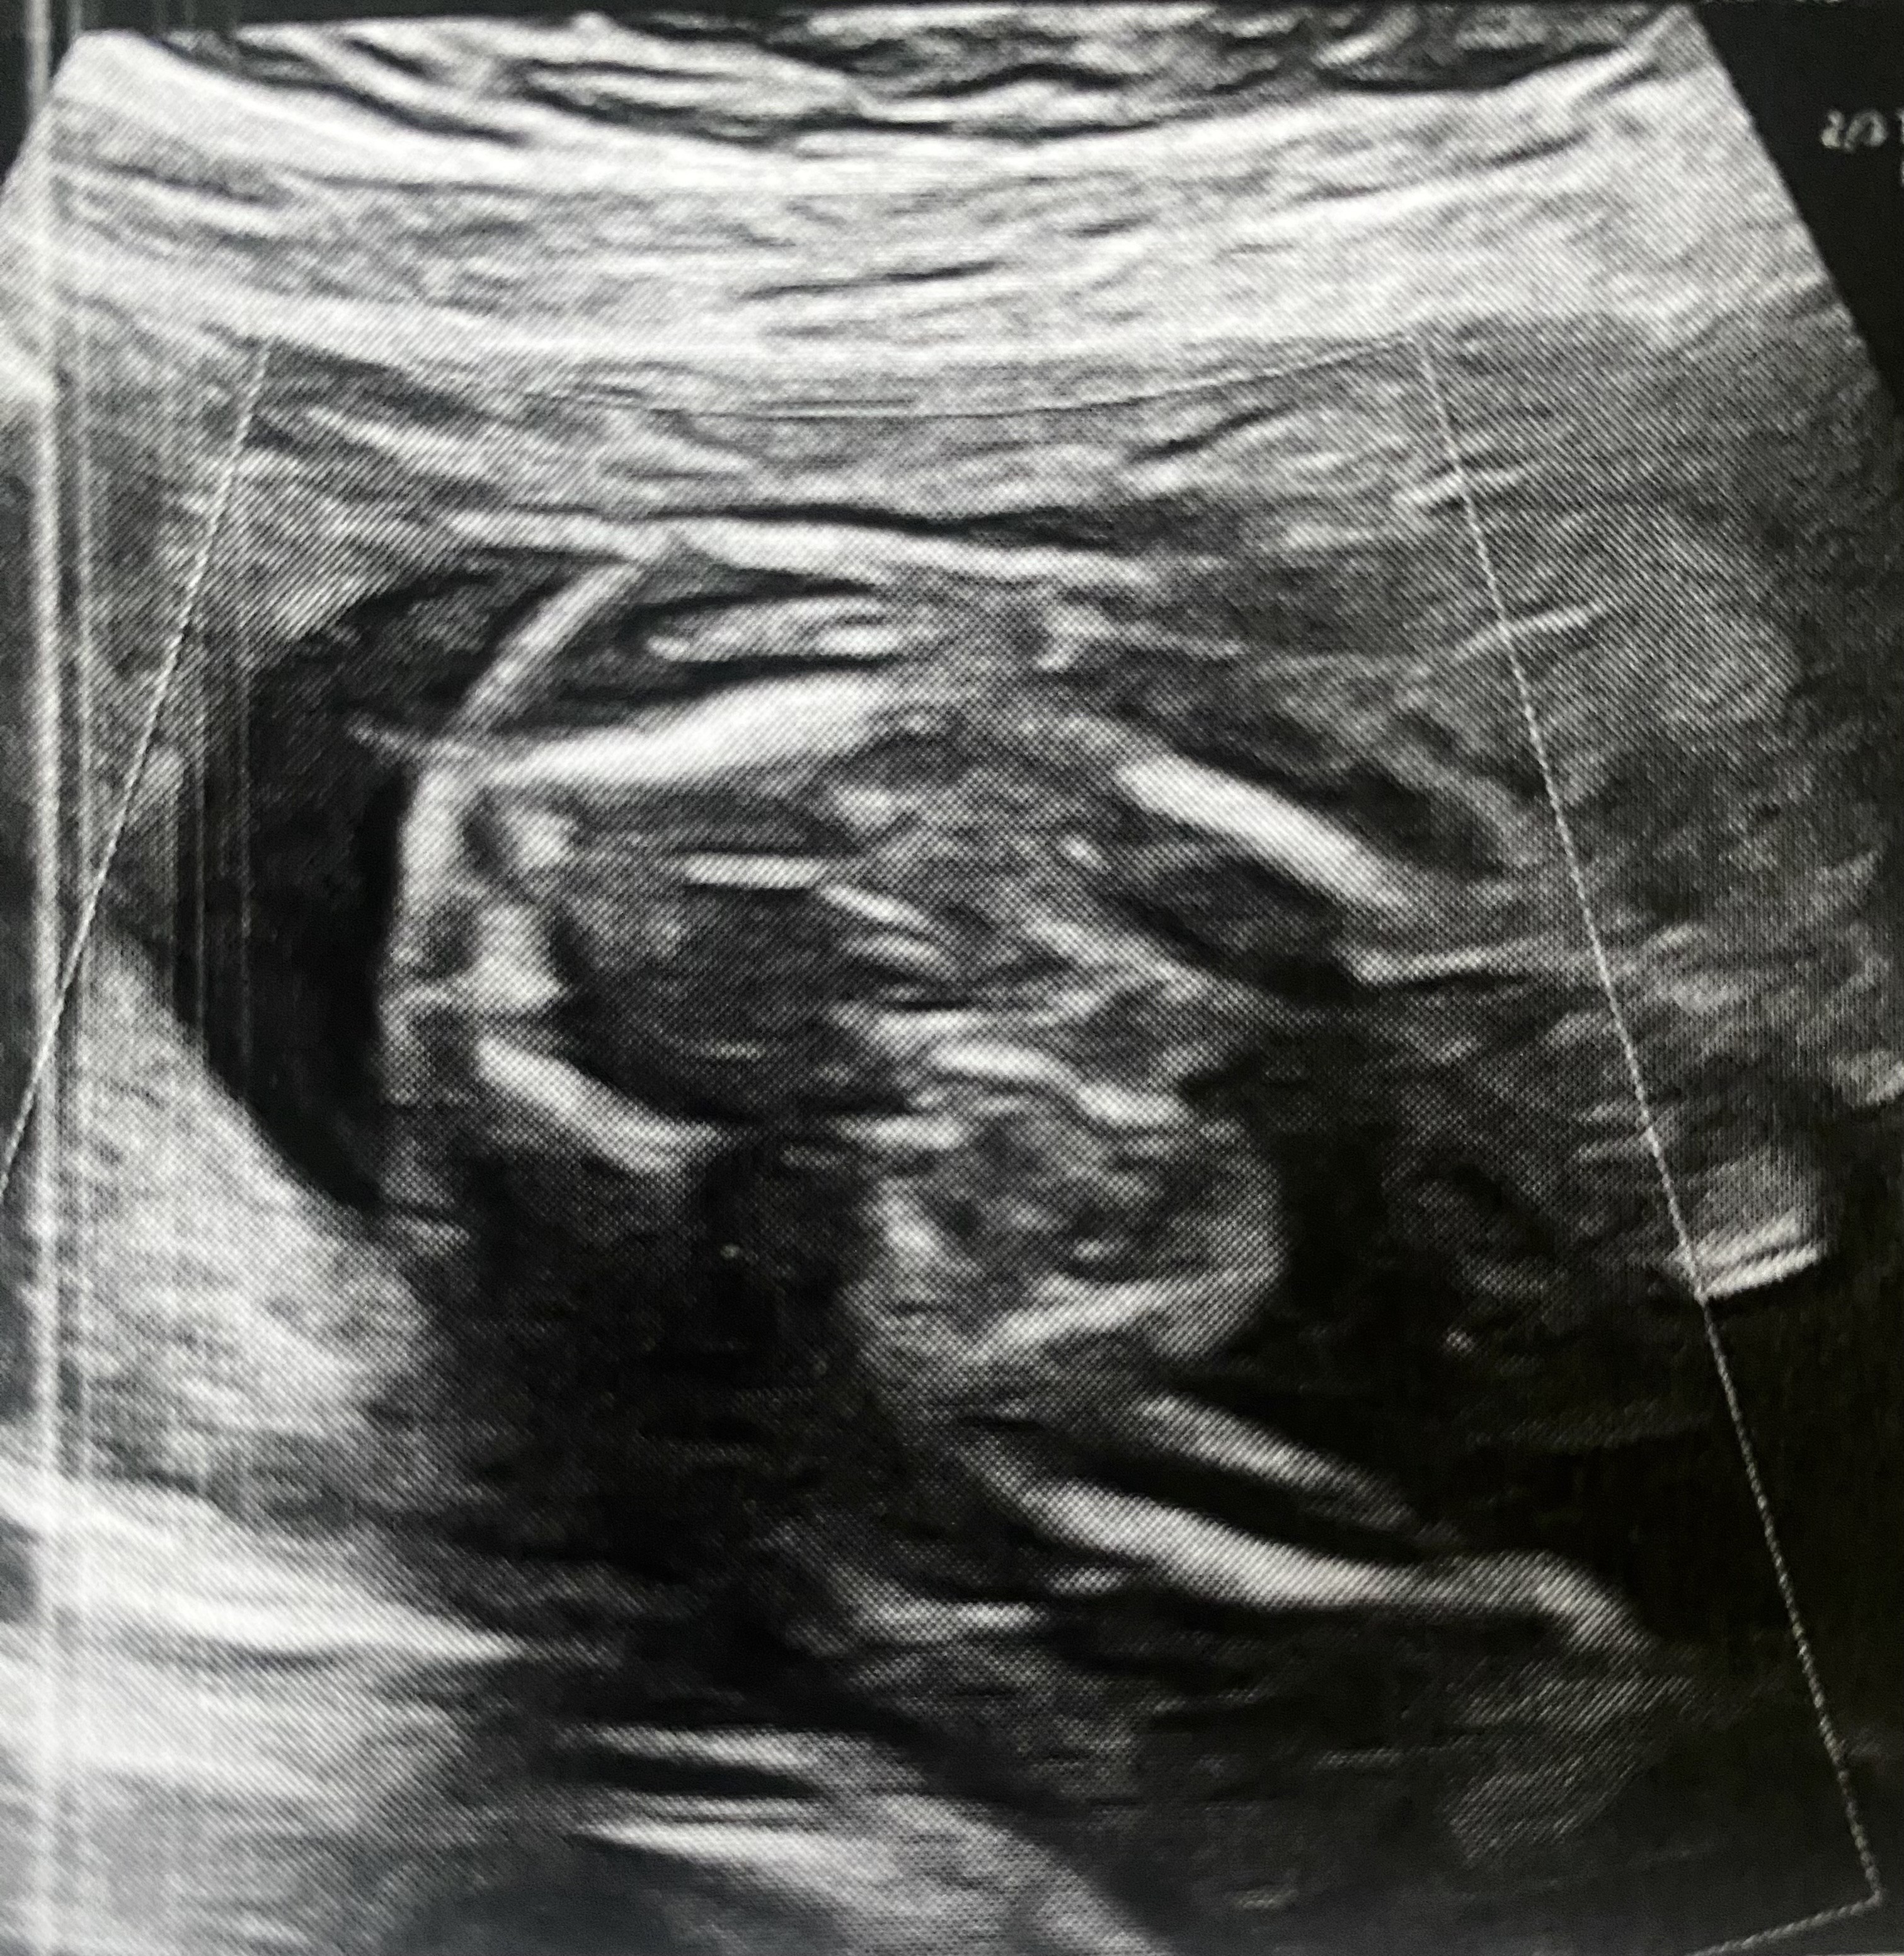

Z ostatniego USG mam tylko takie, chłopiec czy dziewczynka? ;)

Załączniki

• IMG_6255.jpeg

IMG_6255.jpeg

2,2 MB · Wyświetleń: 85